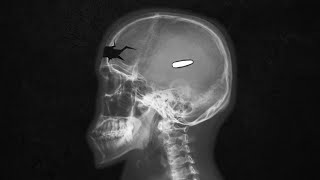

Once in the brain, three things can happen to the bullet. One, it can slow and stop. If it loses enough of its energy when it pierces the skull, it will stop in its path inside the brain, probably at the other end of the skull.

Two, it passes cleanly through, or three, a ricochets inside the head. Of the three, the least common is the third, accounting for about 20% of all bullet paths. If the round was fired from a high-powered rifle, it will most likely pass through.

If it's fired from a pistol, it will likely stop in the brain or ricochet. Also, interesting fact: Most skull ricochets aren't like this, or the bullet bounces off at an angle - though it does happen, but not frequently. In the majority of ricochets, the bullet follows the round groove of the skull.

The skull is actually very strong, and the bullet, having lost so much energy passing through, simply glides along the groove, sometimes sitting just beneath the scalp. Finally, what happens to the brain in this whole ordeal? Well, it's bad.